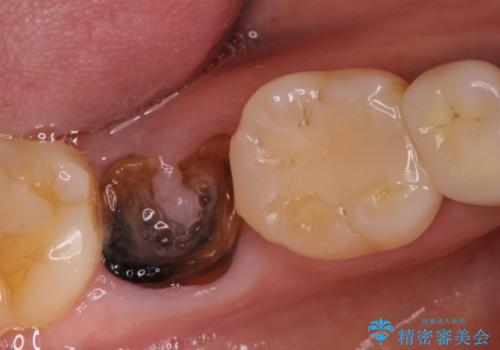

右下の奥歯を抜歯 インプラント治療による咬合回復

- 右下の奥歯をかぶせ物がとれたまま放置しているところに歯を入れたいとのことで来院されました。

精査すると保存が難しいため抜歯をして、インプラントを埋入、かぶせ物を装着する計画としました。